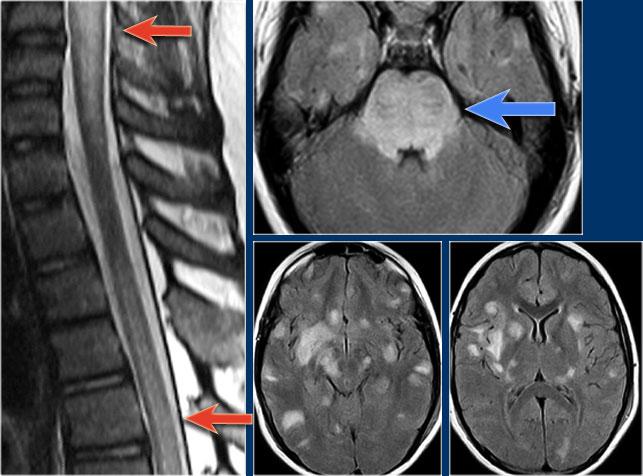

Hình ảnh bên trái của một trẻ vị thành niên với bệnh sử điển hình:

- Ba tuần sau nhiễm trùng đường hô hấp, khởi phát đột ngột các triệu chứng thần kinh.

-

Loạn vận ngôn, khó nuốt, liệt tứ chi.

Rối loạn vận nhãn và rối loạn ý thức.

Bệnh sử lâm sàng này điển hình cho ADEM.

Thông thường não cũng bị tổn thương.

30% trường hợp có tổn thương tủy sống.

Các đặc điểm hình ảnh trong trường hợp này cũng rất điển hình.

Có hình ảnh phù nề và tổn thương tủy tương tự như trong viêm tủy ngang (TM) và không có ngấm thuốc.

Tiếp tục xem các hình ảnh của não.

Trước tiên hãy quan sát các hình ảnh não và xác định điểm khác biệt so với tổn thương trong MS.

Những đặc điểm điển hình cho ADEM và ít gặp trong MS là:

- Tổn thương lan rộng vùng cầu não.

- Tổn thương hạch nền.

Hình ảnh MRI theo dõi cho thấy tủy sống đã trở về bình thường.

Bên trái là một trường hợp ADEM khác.

ADEM thường gặp ở trẻ em.

Một lần nữa có hình ảnh tổn thương lan tỏa tủy sống không ngấm thuốc và có tổn thương não kèm theo.

Một trường hợp ADEM khác.

Lưu ý hình ảnh tổn thương điển hình vùng cầu não và hạch nền.

Tiếp tục xem hình ảnh theo dõi.

Hình ảnh theo dõi cho thấy gần như bình thường hóa hoàn toàn.